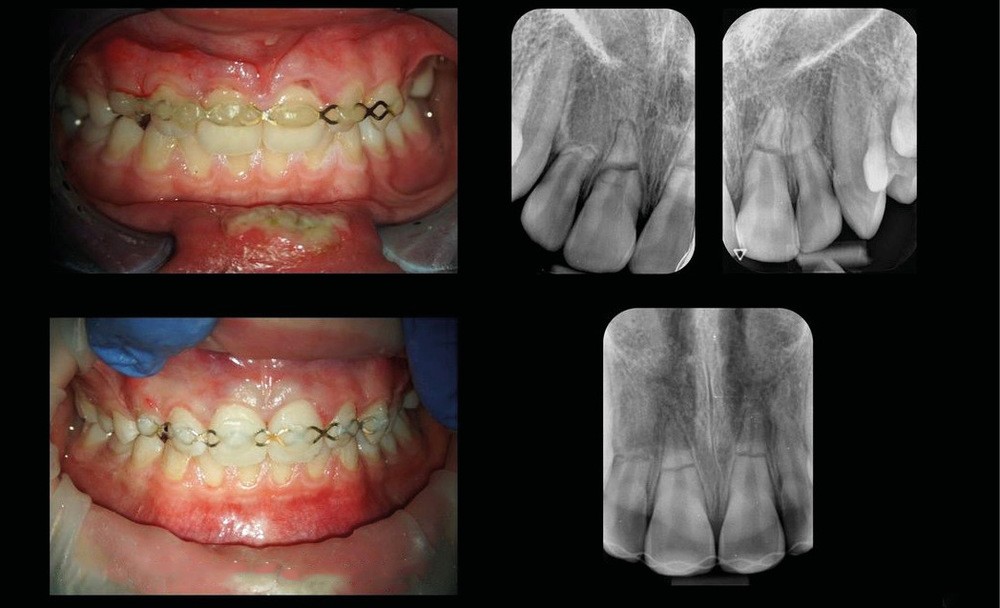

La fig. 1 montre la situation clinique le jour du traumatisme. Les photographies et radiographies permettent d’observer des factures radiculaires des 4 incisives ainsi que, au minimum, la luxation de la 11. Deux fractures radiculaires horizontales importantes au niveau de la 11 et de la 21 sont notées. Une fracture moins marquée radiologiquement au niveau de la 22 et une résorption apicale au niveau de la 12 sont visibles. Cette dernière est probablement antérieure au traumatisme du jour. Le patient est d’abord pris en charge par un dentiste de garde qui pose une attelle (fig. 2). Il est ensuite référé pour une prise en charge en endodontie.